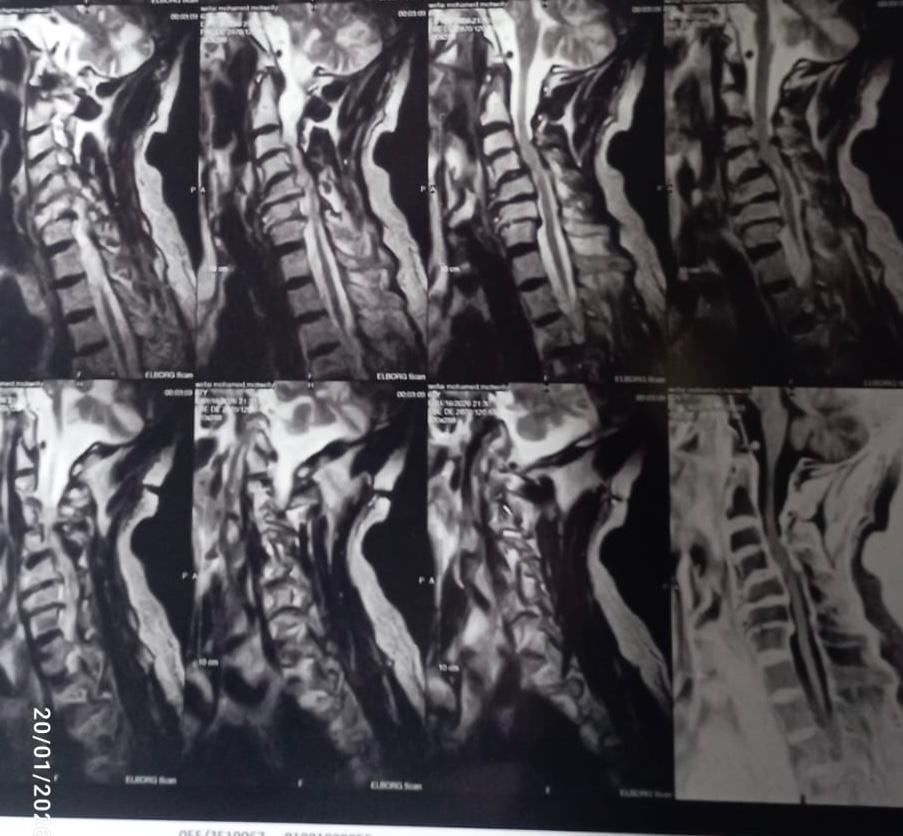

وبإجراء الفحوصات الطبية والأشعات اللازمة، تبين إصابة المريض بانزلاق غضروفي عنقي متعدد على أربعة مستويات، ما أدى إلى حدوث كدمة بالحبل الشوكي وضيق كامل بالقناة الشوكية العنقية، وهي من الحالات شديدة الخطورة التي تستدعي تدخلاً جراحيًا دقيقًا وعاجلًا.

وعلى الفور تم تجهيز الحالة طبيًا من خلال إجراء جميع الفحوصات والتحاليل اللازمة، قبل أن يخضع المريض لجراحة ميكروسكوبية دقيقة ومعقدة، تم خلالها استئصال الغضاريف المنزلقـة، وتركيب أقفاص عنقية مثبتة بدعامات ذاتية (Stand-alone) على أربعة مستويات، وذلك باحترافية عالية، مع خروج المريض من غرفة العمليات في حالة مستقرة وآمنة.

وأكد الفريق الطبي، أن الحالة شهدت تحسنًا ملحوظًا بعد الجراحة، تمثل في تحسن تام بحركة الأطراف الأربعة، وتحسن واضح في قوة الأعصاب، بالإضافة إلى تحسن التحكم في البول والبراز، مع استمرار تلقي الرعاية الطبية اللازمة داخل المستشفى لاستكمال فترة النقاهة والمتابعة.